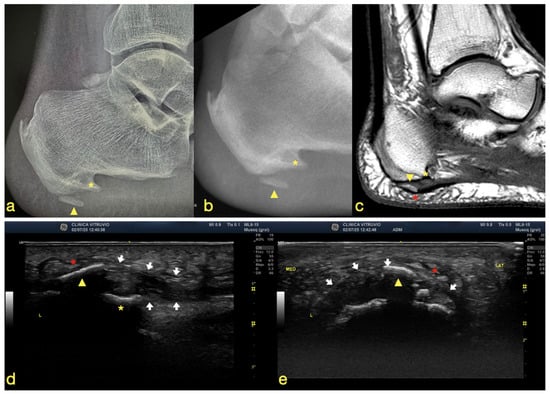

The total cutting time was 6 min and 29 s, during which complete removal of the ossified tissue was achieved (Figure 3). Within 48–72 h after the procedure, the patient reported marked relief of the characteristic sensation of “walking on a stone.” At the 1-month follow-up, he demonstrated a significant improvement in pain symptoms, with progressive recovery of function.

Figure 3. Fluoroscopic images showing (a) the preoperative view and (b) the postoperative view. The yellow asterisk indicates the calcaneal spurs (enthesophytes), and the yellow arrowhead denotes the heterotopic ossification.